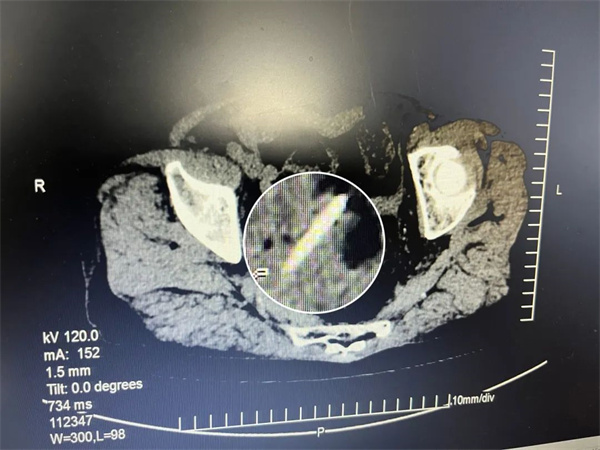

75岁的曾婆婆,特别爱吃鱼,虽说是吃鱼老手,可也有百密一疏的时候。那天,曾婆婆一如既往吃鱼,结果鱼刺顺着喉咙吞了下去,十多天后曾婆婆总觉得“上腹部疼痛不适”,于是来到犍为县中医医院就诊,随后收入外科住院,综合检查后诊断为:乙状结肠穿孔、穿孔性腹膜炎、冠状动脉粥样硬化性心脏病、冠状动脉支架植入后状态。主治医师纪显春判定腹腔里的异物就是鱼刺,而且极有可能已经扎穿肠壁,导致严重的腹膜炎,如果不抓紧处理,万一鱼刺钻出肠道刺破大血管,患者随时都会有生命危险。

与患者及家属充分沟通后,外科医护团队立即联合手术室急诊在全身麻醉下行腹部探查术,术中可见腹腔内产生了大量脓性液,乙状结肠与直肠交界处上方见网膜与肠管之间形成一脓肿,清除脓肿后发现一根长约4.0cm的鱼刺刺破大肠,导致大肠穿孔而引起的继发性腹膜炎,由于肠穿孔时间较久,经过层层剥茧, 终于,一根扎穿大肠的鱼刺被顺利取出。